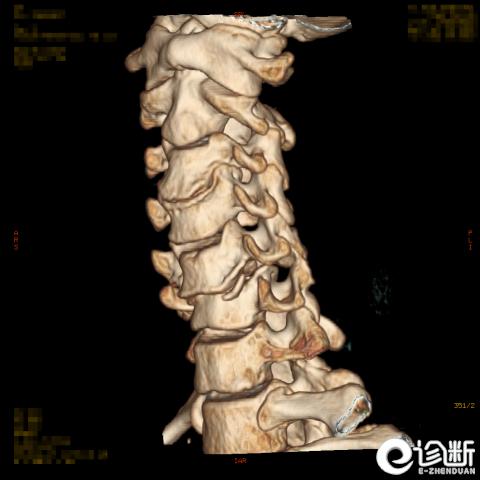

颈椎骨折

CT:显示椎管(骨折碎片可压迫椎管)

根据骨折的水平及位置:C1-Jeferson骨折:前后弓骨折

C1-侧块骨折

C2-Hangman骨折(峡部):Levine分型

C2齿突骨折1型、2型、3型

C3-7骨折: